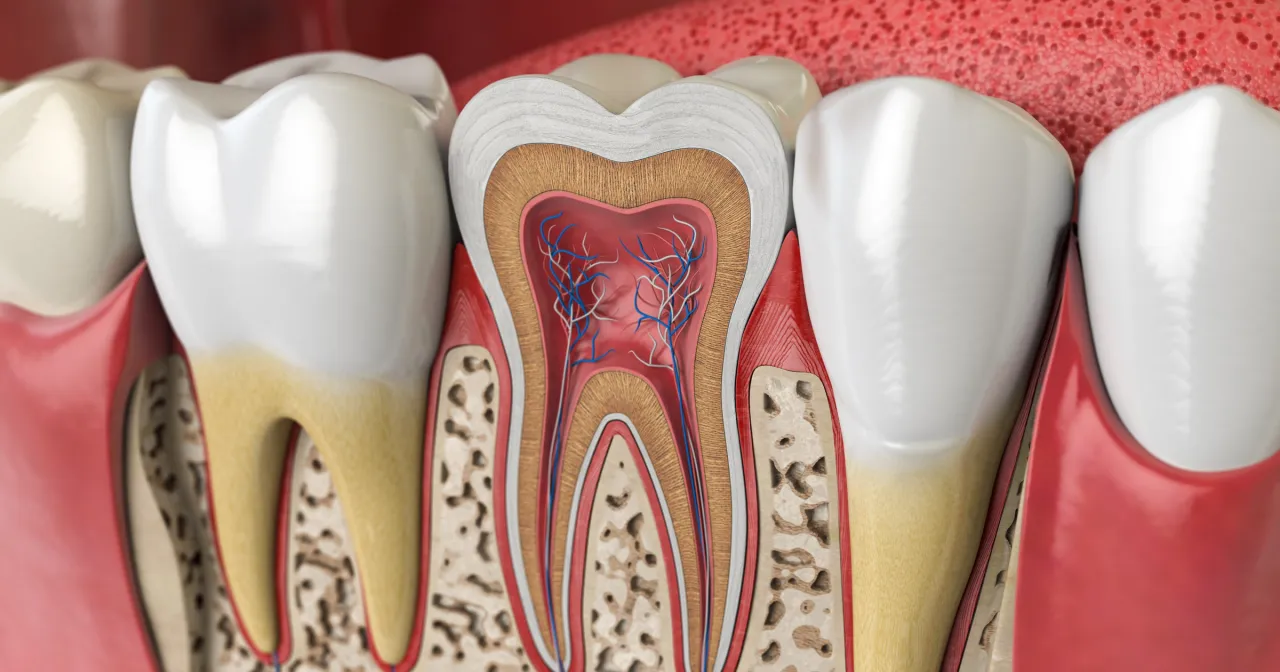

Korzenie zęba 5 górna mają kilka unikalnych cech, które odgrywają kluczową rolę w jego funkcjonowaniu. Zazwyczaj są one trzy, ale mogą występować również w liczbie dwie. Korzenie te są dość długie i mają różne kształty, co sprawia, że są dobrze przystosowane do ich funkcji. Zwykle jeden z korzeni jest dłuższy, a pozostałe są krótsze, co pozwala na stabilne osadzenie zęba w szczęce.

W przypadku górnego zęba 5, korzenie są również lekko zakrzywione, co zwiększa ich powierzchnię kontaktu z kością szczęki. Taki kształt sprzyja lepszemu unieruchomieniu zęba i jego prawidłowej funkcji podczas żucia. Często można zauważyć, że korzenie mają różne średnice, co również wpływa na ich funkcjonalność. Warto zwrócić uwagę na te cechy, ponieważ mogą one mieć znaczenie w kontekście leczenia stomatologicznego.

| Cechy korzeni | Opis |

|---|---|

| Liczba korzeni | Najczęściej dwa lub trzy |

| Kształt | Długie, lekko zakrzywione |

| Stabilność | Dzięki różnym średnicom i długościom korzeni |